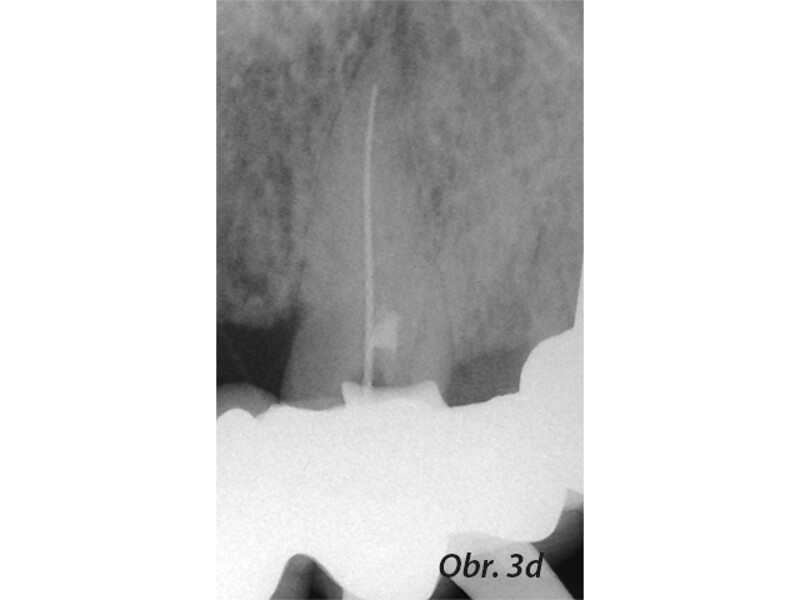

Aplikace MTA s použitím Produit Dentaires (PD) MAP System